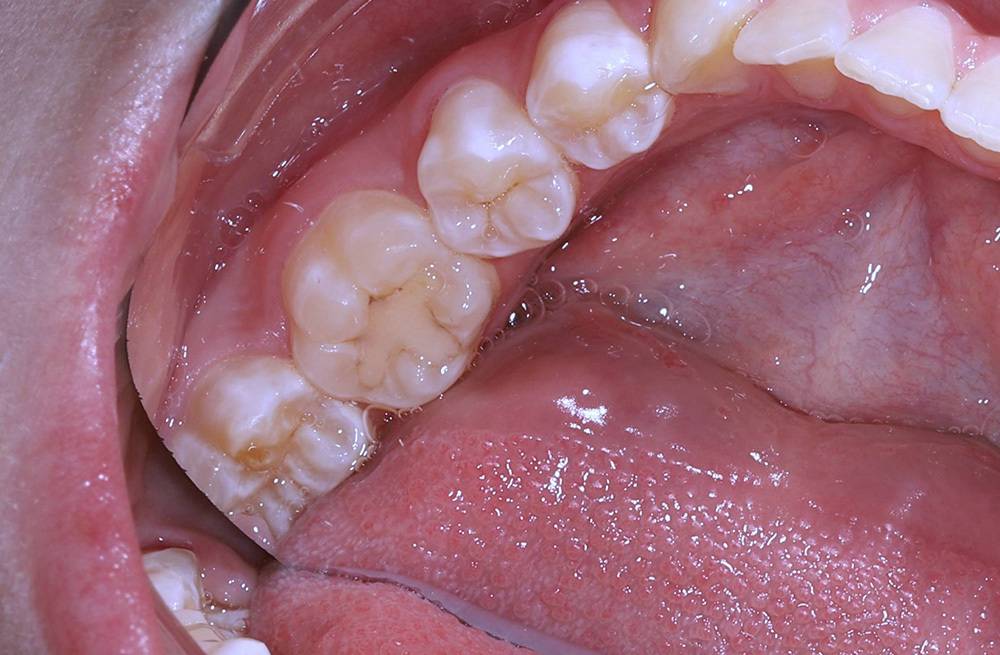

Замена негерметичной старой пломбы и лечение кариеса на соседнем зубе у подростка с жалобами на боль от сладкого